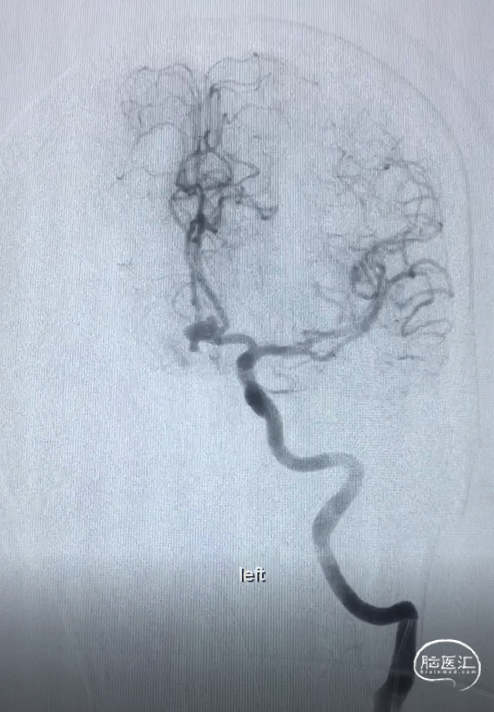

术前DSA:LICA正侧位及工作角度造影显示前交通动脉瘤